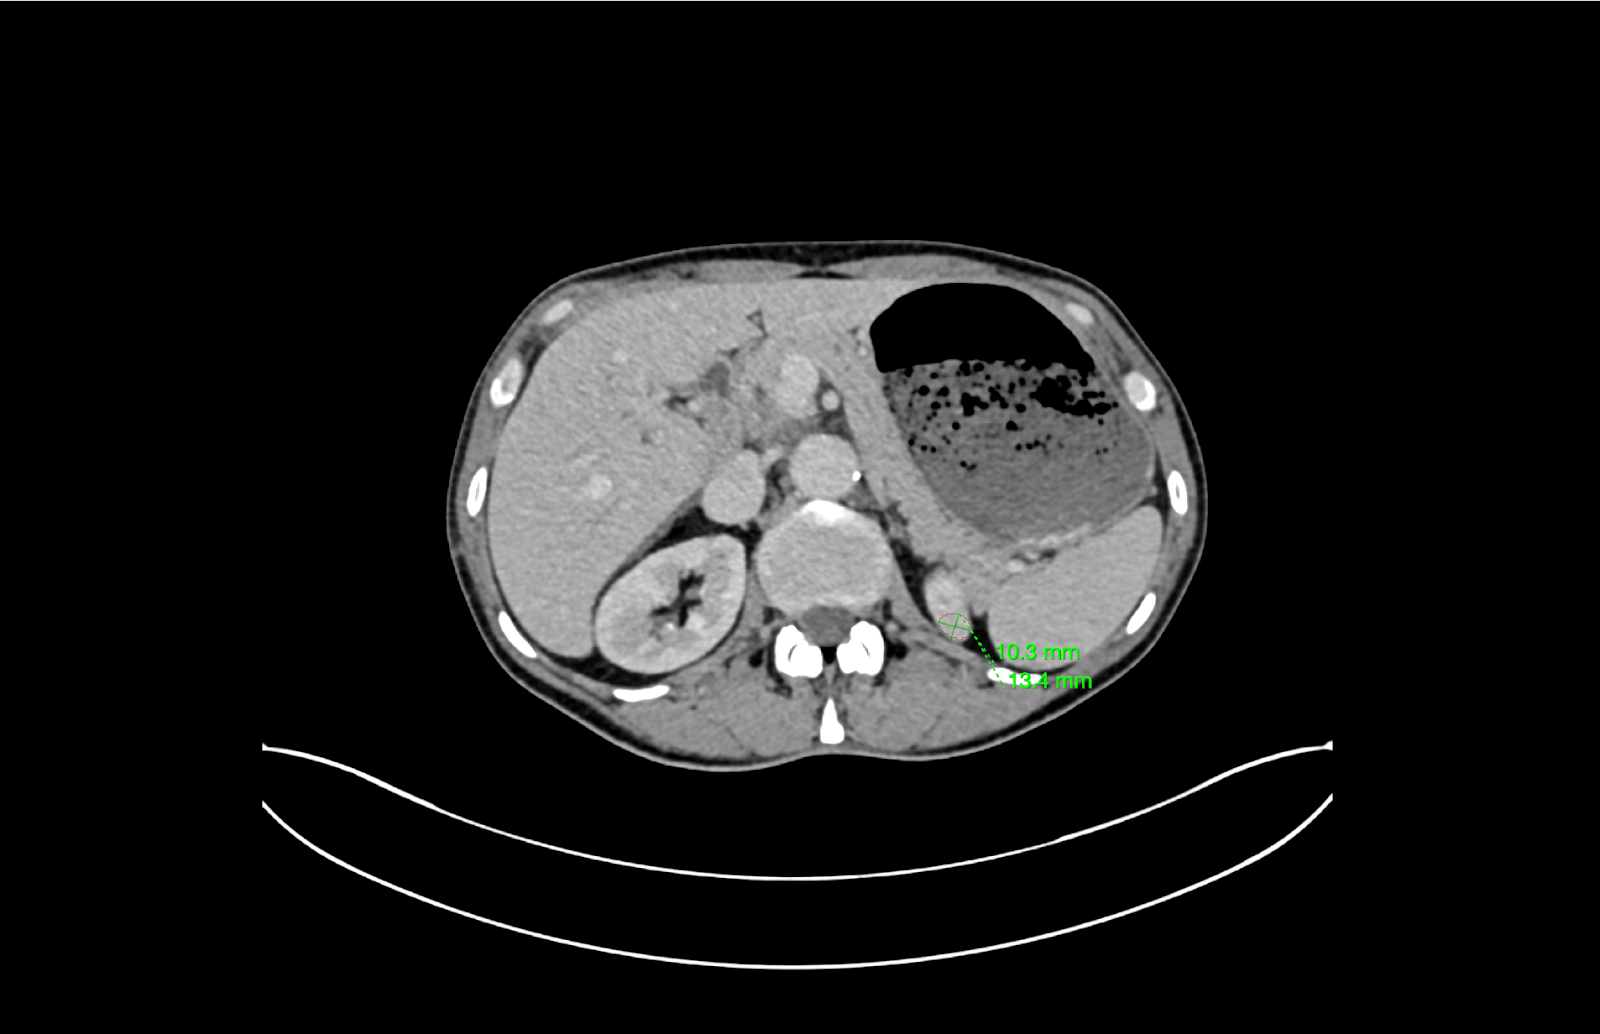

Better Medicine provides an AI-powered radiology solution, BMVision Kidney, designed to enhance diagnostic consistency and speed in kidney cancer detection. It is the first and only CE-certified AI model specifically trained to identify renal tumours from CT scans.

The software runs fully on-premise within UMC’s infrastructure, integrates with existing PACS and viewer systems, and processes CT data in standard formats to deliver interpretable results. Using advanced deep learning, BMVision Kidney automatically detects, segments, and characterises kidney lesions—including incidental findings—with accuracy comparable to radiologists. The solution strengthens diagnostic reliability, reduces variability, and supports faster, more consistent clinical decision-making within UMC’s radiology workflow.